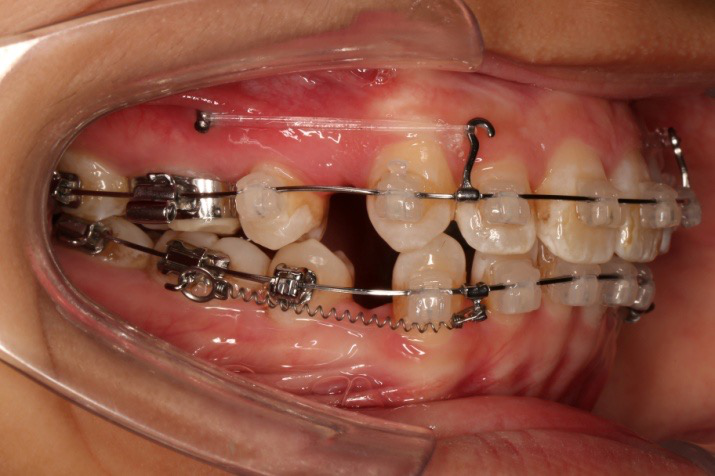

2016.10.31  初戴,0.013cu-niti2017.1.13  上颌加TPA,U56间斜形植入韩国庆北1312-08种植钉,上下0.16cu-niti

2017.02.16  上下0.014*25 cu-niti,50g 拉尖牙远中

2017.04.28

2017.04.28  上0.016*25ss 13、23近远中约5度 v形曲,下0.017*25ss

2017.05.26  磨牙近中倾斜,下颌36、46加power arm

2017.07.25

2017.07.25  上前牙加颈部弹力线